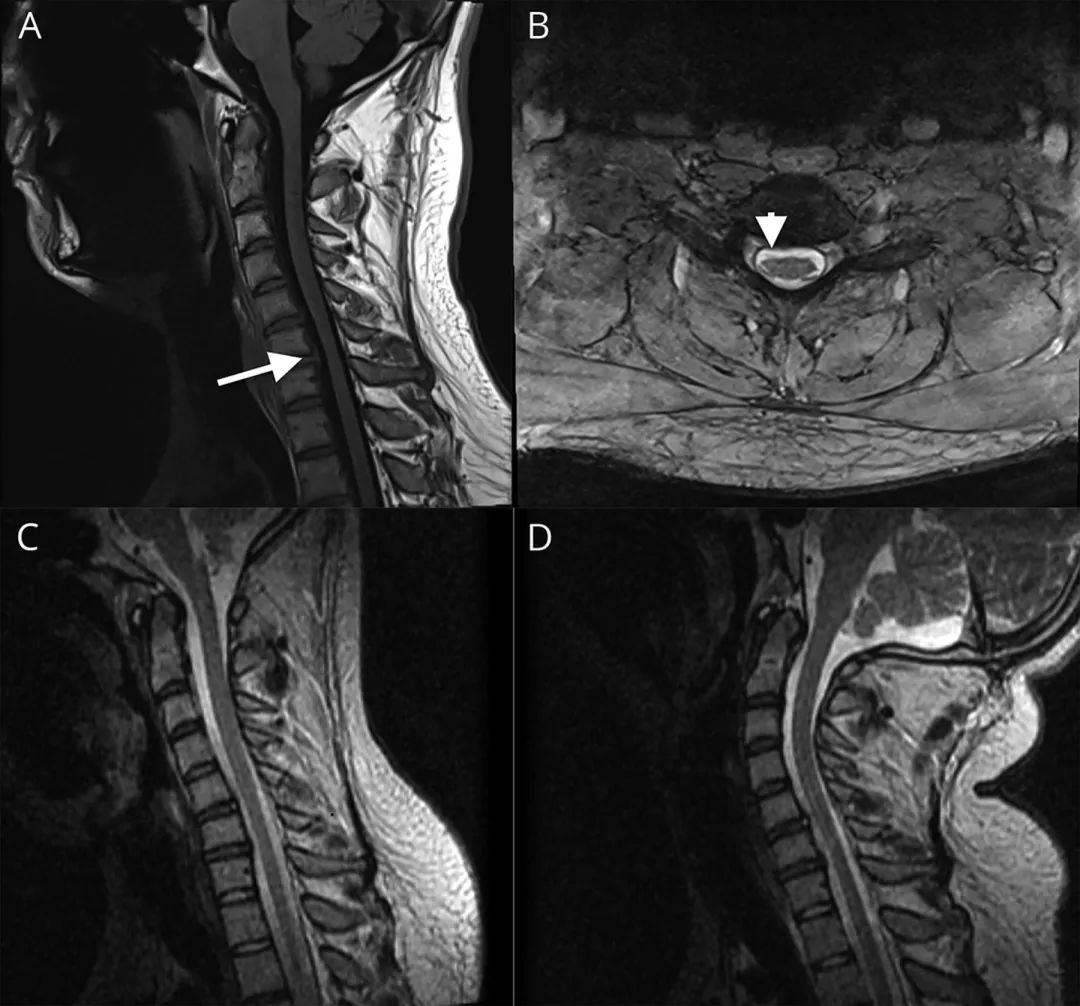

发病后2年的颈椎MRI显示C5-C7脊髓轻度萎缩,C5-C6轻度退行性椎间盘病变(图1 A,B)。头颅MRI检查正常。神经传导检查正常,但第一背侧骨间肌、小指展肌(ADM)、桡侧屈腕肌和肱三头肌可见高波幅、长时限、多相运动单位,EIP中未见插入或自发电活动。2周后复查电生理进一步证实上述表现,同时在EIP、拇长屈肌和肱三头肌可见纤颤电位和正锐波。左内侧前臂皮肤感觉、左侧尺运动和左侧ADM的EMG均正常。上述结果提示不对称的慢性神经源性病变。

图1 患者影像结果。(A)T1加权液体衰减反转恢复矢状位图像显示C5-C7颈髓扁平。(B)T2加权轴位图像显示右侧颈髓扁平程度大于左侧。T2加权矢状屈曲位(C)和伸展位(D)图像未显示椎体压迫脊髓; 但也有可能颈部未达到最大程度的屈曲位。

震颤常代表多发小的肌阵挛(polyminimyoclonus),在JMA和其他运动神经元疾病中有报道。屈曲和伸展位颈椎MRI(图1 C,D)再次证明右侧颈髓扁平,只有轻微的椎间盘突出或神经根压迫。脑和臂丛的MRI检查正常。电生理检查显示除了右侧屈指深肌可见纤颤、正锐波和肌强直放电外,基本没有改变。